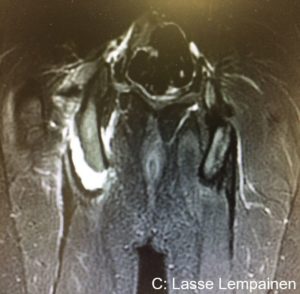

Figures 5-7. Central tendon rupture of the biceps femoris with clear retraction. Peroperative view before and after repair.

It has been suggested that central tendon injuries especially in the BF may have a higher risk of poor healing with conservative treatment. Also the risk of a recurrent injury may be high. In these injuries there is often an incomplete tear of the paramuscular tendon typically in the area of 5 to 20 cm from the proximal origin (Figures 5, 6 and 7). Often the muscle tissue is torn off from the tendon also. When a tear like this remains symptomatic after adequate conservative treatment or there are recurrences surgery should be considered. Full continuity of the central tendon is restored with sutures and the attachment of the muscle to the tendon is reinforced. It is important to avoid overthightening of the repaired tendon. Scar tissue may be removed. Suture anchors may be used if the tear is located close to the bony origin.